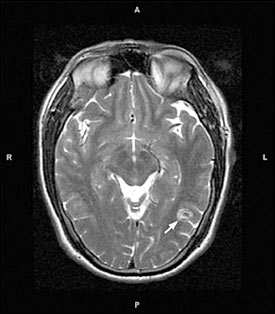

Sau khi thăm khám và điều tra bệnh sử, chụp cắt lớp vi tính có hoặc không có bơm thuốc cản quang đường tĩnh mạch là bước đầu tiên trong chẩn đoán các ca bệnh nghi ngờ ATSL thần kinh. CT não có hoặc không có thuốc cản quan sẽ cho thấy hình ảnh các tổn thương điển hình của ATSL đường kính nhỏ hơn 20mm và không có hình ảnh phản đứng giữa (no midline shift) là hình ảnh gợi ý cao cho thể ATTSL thần kinh (neurocysticercosis). Phần scolex, hoặc phần giác hút của ấu trùng cũng có thể nhìn thấy; đây là đặc trưng bệnh của ATSL thể thần kinh.

Hình 2. trên hình ảnh CT có nang của ATTSL thể thần kinh trong nhu mo não đặc | Hình 3. hình ảnh cộng hưởng từ cho thấy các nang của ATSL thể thần kinh trong nhu mô |

Số lượng, kích thước và vị trí có nang xuất hiện cũng như giai đoạn chu kỳ của nang sán, có thể xác định và có thể tác động đến việc quyết định điều trị. Các nang là các hình ảnh tổng thương dạng điểm có thể phát triển và tồn tại được, nang không bị thoái hóa. Các tổn thương dạng nang chỉ ra biến tính hoặc thoái hóa có một vài phản ứng viêm bao quanh. Cuối cùng, các nang hình thành calci hóa là một bằng chứng các nang đã tồn tại lâu có thể đã chết. Chăm sóc phải được tiến hành khi có thể còn nghĩ đến nhiều nguyên nhân khác (lao, bệnh ký sinh trùng khác, di căn từ nơi khác đến, hoặc ung thư nguyên phát của não hoặc hình ảnh abces não) khi một tổn thương tìm thấy trên phim chụp cắt lớp.

Hình ảnh trên phim chụp cộng hưởng từ cũng là công cụ hữu ích để chẩn đoán ATSL thể thần kinh và có thể tốt hơn cả chụp cắt lớp CT để phát hiện các thương tổn trong não tủy, trong cuống não, trong não thất. Việc áp dụng nó nên cân nhắc khi CT không chẩn đoán ra. CT và siêu âm là rất nhạy để phát hiện các tổn thương ATSL tại mắt và hệ cơ xương.